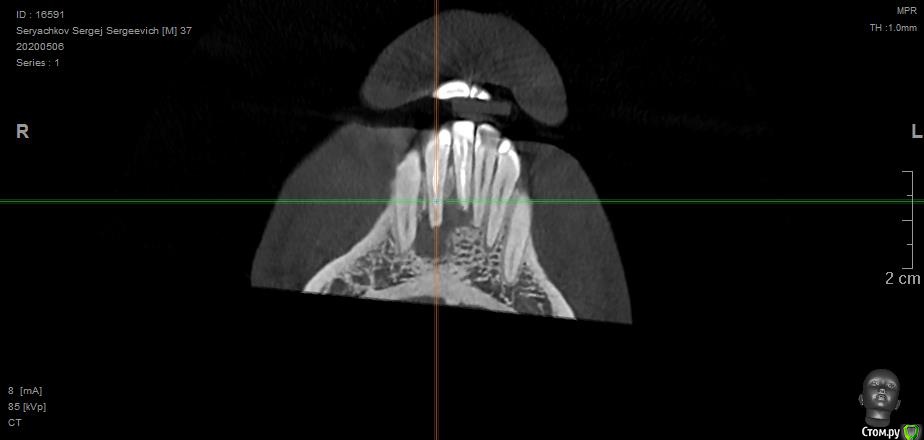

Под передними резцами обнаружилась обширная киста. В трёх клиниках предложили различное решение, но все основаны на удалении двух зубов, под которыми киста. Есть ли вариант сохранить и полечить зубы или удаление неизбежно?